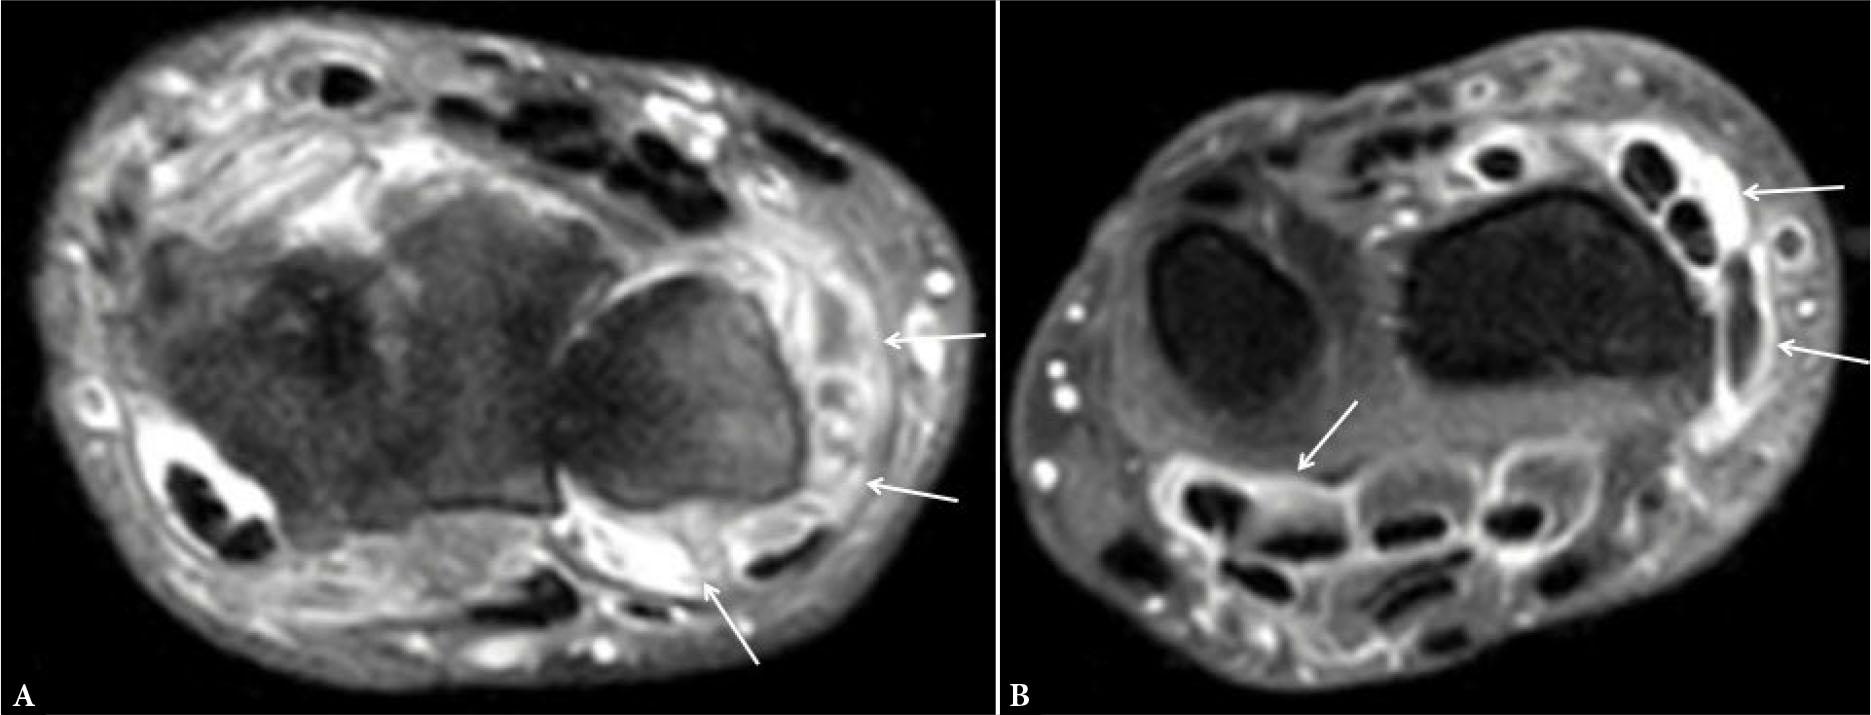

On MRI, SH appears as thickened synovium, and it is hyperintense on T2-weighted images, which makes it difficult to differentiate it from effusion. Consequently, contrast administration can be useful to distinguish enhancing synovium from non-enhancing effusion (Fig. 6). Synovial enhancement should be examined within 10 minutes from contrast administration, after which the contrast agent diffuses into the synovial fluid(9). MRI can be used to quantify synovial volume, which has been shown to correlate with disease activity(10).

Axial post-contrast T1-weighted (T1W) fat-suppressed image of the distal radioulnar joint shows enhancing synovium (arrows in A), suggesting synovitis along with enhancement of the flexor and extensor tendon sheaths (arrows in B), consistent with tenosynovitis

On MRI, bone erosions are sharply marginated bone defects that are seen in at least two planes, with a cortical break visualized in at least one plane with low signal intensity on T1-weighted images(9,17) (Fig. 9). Histologically, they represent localized replacement of bone marrow fat by inflammatory cells adjacent to a cortical bone barrier(18). The fluid or inflammatory tissue within the erosion appears hyperintense on T2-weighted images and may show enhancement on post-contrast T1-weighted images (Fig. 9).

Erosions. Axial T1-W MR image of wrist joint reveals hypointense bony defects in the carpal bones (arrows in A) showing enhancement on post-contrast T1-W fat-suppressed image (arrows in B). Erosions in such locations can be missed on US